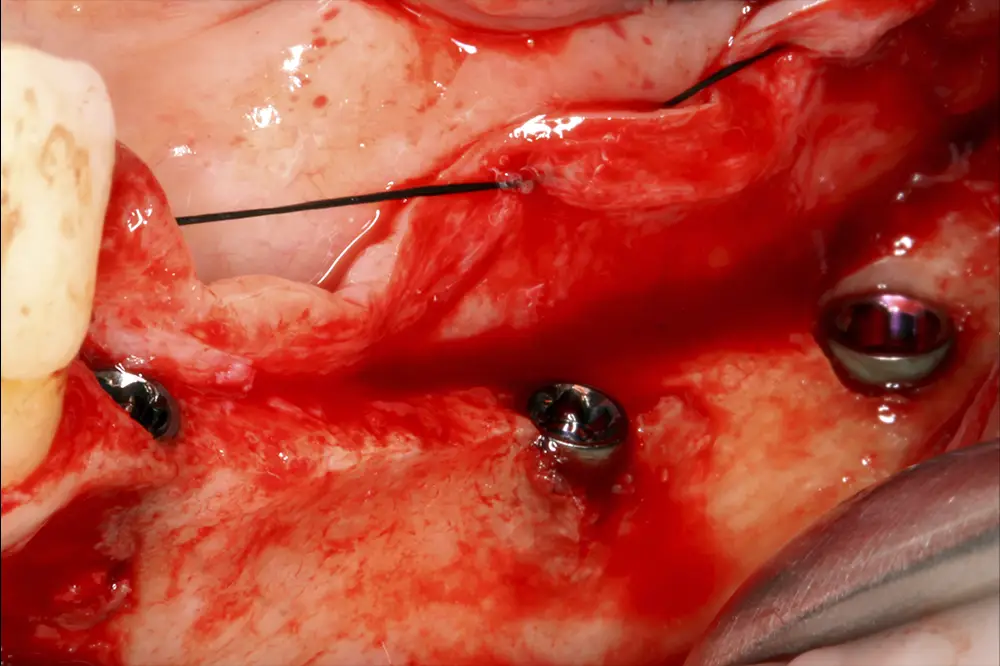

Figuras 16 y 17. Implantes colocados tras la cirugía.